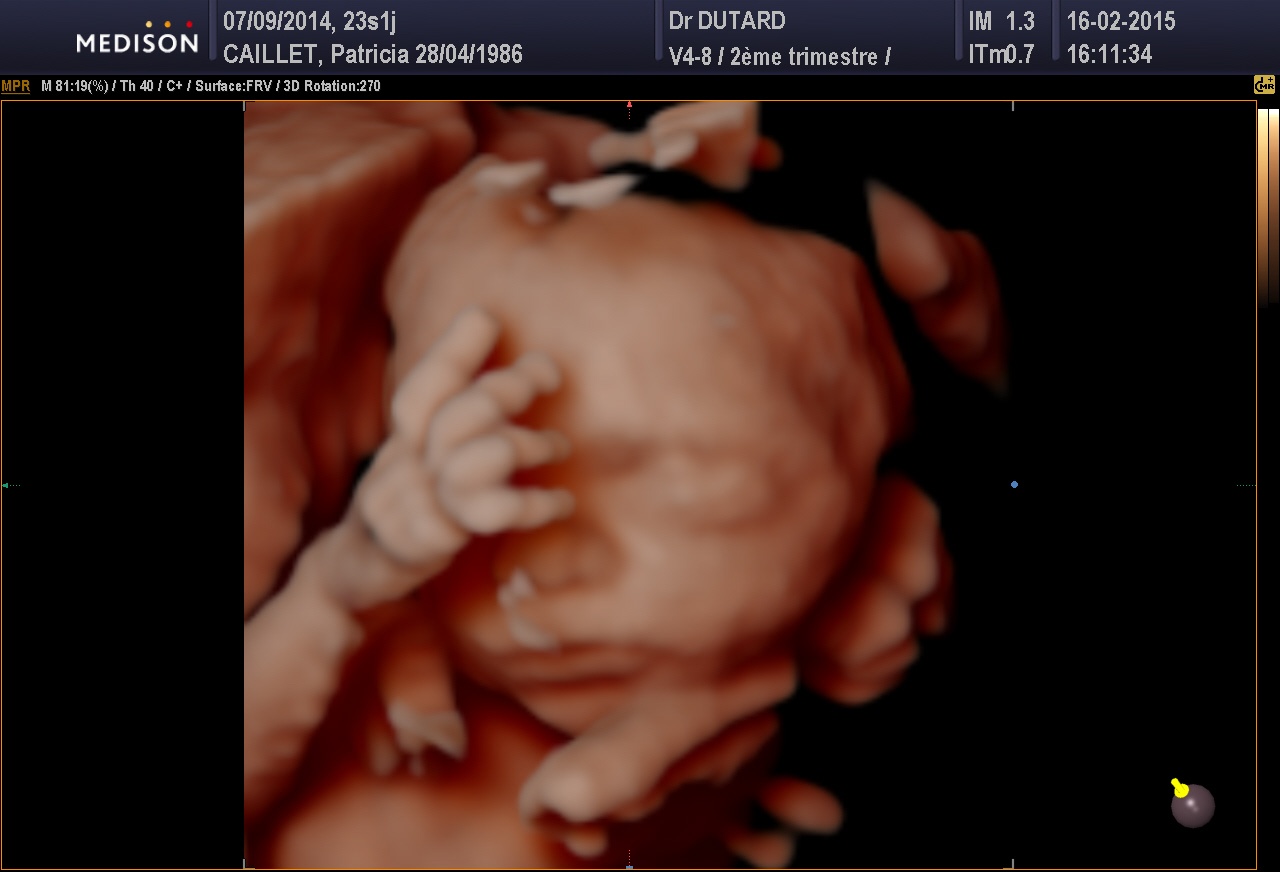

de son ptit bonhomme,puis on s en lasse pas de regarder ses echo surtout en 3d c est le top